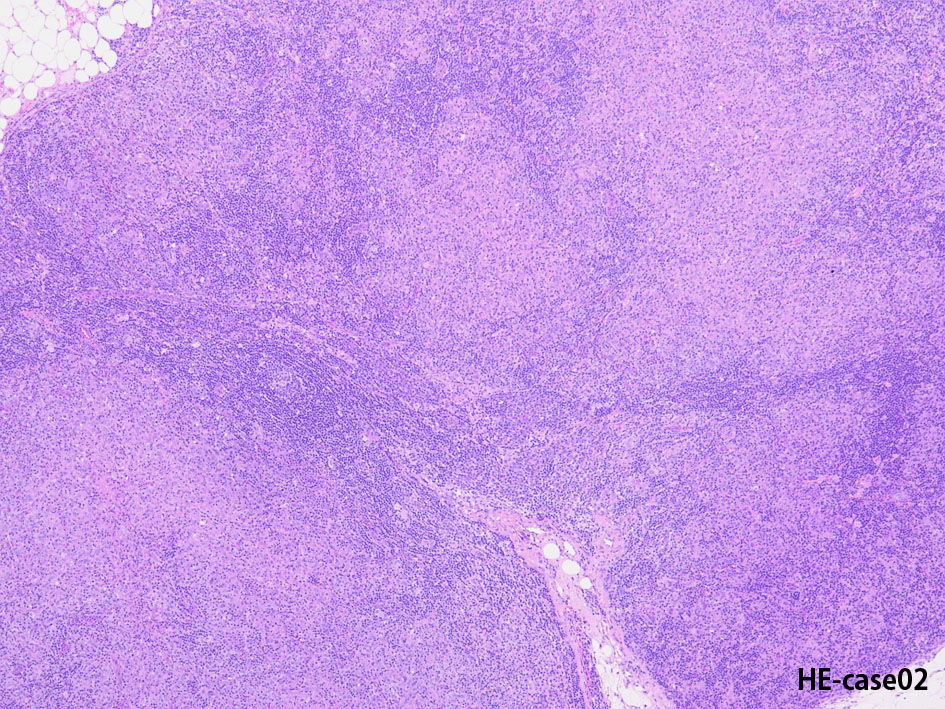

Hodgkin lymphoma-Case02-IWT

74歳男性 左頚部リンパ節腫大

組織球が類上皮細胞様に集蔟して肉芽腫様病変を形成, リンパ節内に明るく見えるエリアができている。HRS細胞が散在。背景はリンパ球, 形質細胞。好酸球が多く見られる

免疫染色

CD30, CD15は陽性, 転写因子のBob.1, OCT2は腫瘍細胞は陰性となる.